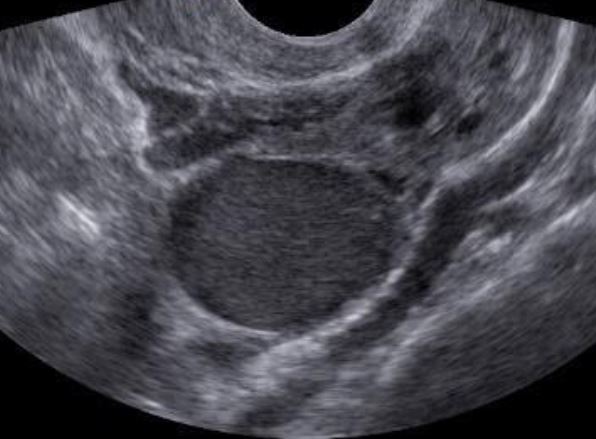

Endometriose no ovário

A endometriose no ovário se caracteriza pela presença de um cisto ovariano, chamado endometrioma.

O conteúdo dos endometriomas é sangue proveniente dos focos de endometriose, que todo mês determinam sangramento para o interior da cavidade do cisto aumentando o tamanho do cisto.

A hemoglobina contida no interior destes cistos está mais degradada que a hemoglobina proveniente de sangramentos mais recentes, como por exemplo nos cistos de ovulação (cistos hemorrágicos), possibilitando desta forma o diagnóstico pelos métodos de imagem.

Endometrioma caracterizado no ultrassom transvaginal com preparo intestinal